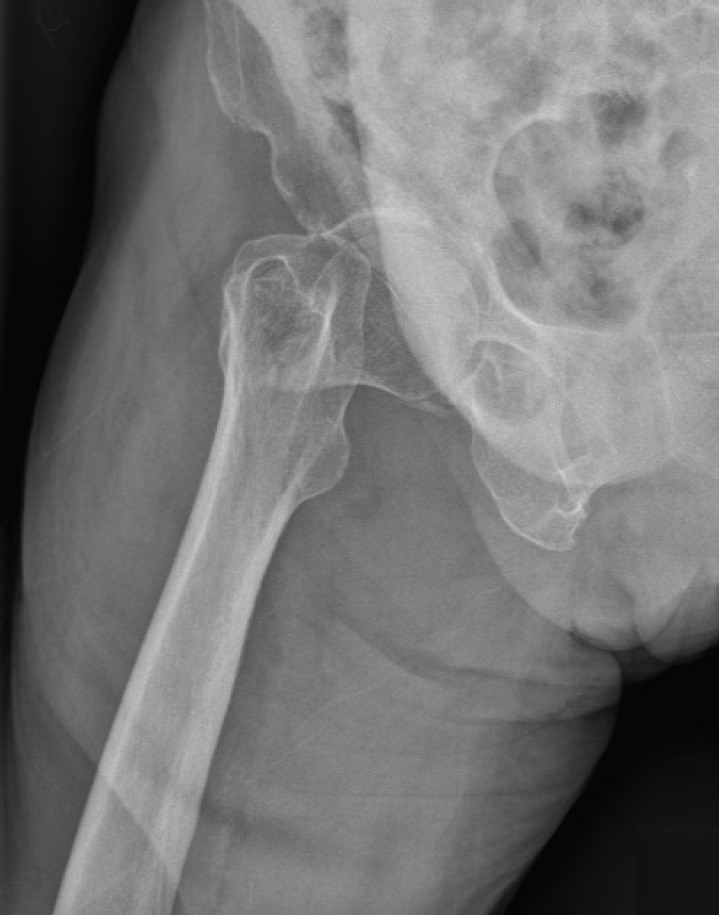

股骨颈骨折常见于老年患者,通常需要手术干预以迅速恢复活动能力并减少并发症。虽然前路、外侧路和后路常用于半关节置换术,但每种入路都有其优缺点。值得注意的是,在一些研究中,后路入路与较高的脱位风险有关。SPAIRE(保留梨状肌和内肌,修复外肌)技术是传统后外侧入路的现代适应。这种微创、解剖上考虑周到的方法保留了梨状肌肌腱和上孖肌、闭孔内肌和下孖肌的联合肌腱。然而,它需要切开闭孔外肌的肌腱。该技术旨在保持肌肉结构稳定,降低脱位风险,加速功能恢复,包括神经系统疾病患者。本病例报告描述了一名79岁女性右股骨颈经颈骨折的治疗。采用SPAIRE技术行双极半关节置换术。该手术有效地保留了梨状肌-关节肌腱(股四头肌髋)的功能协同单位,并包括细致的包膜和肌腱修复。患者术后恢复的特点是在3个月的随访中功能预后良好。本病例强调了SPAIRE技术在增强关节稳定性和促进快速恢复方面的优势,特别是在老年患者中。

Femoral neck fractures commonly occur in older patients and typically require surgical intervention to promptly restore mobility and minimize complications. While the anterior, lateral, and posterior approaches are frequently employed for hemiarthroplasty, each has its own benefits and drawbacks. Notably, the posterior approach has been linked to a higher risk of dislocation in some studies. The SPAIRE (saving piriformis and internus, repair of externus) technique is a modern adaptation of the traditional posterolateral approach. This less invasive, anatomically considerate method preserves the piriformis muscle tendon and the conjoint tendon of the superior gemellus, obturator internus, and inferior gemellus muscles. However, it involves sectioning the tendon of the obturator externus muscle. The technique is designed to maintain stabilizing muscular structures, decrease dislocation risk, and hasten functional recovery, including in patients with neurological conditions. This case report describes the treatment of a 79-year-old woman with a transcervical fracture of the right femoral neck. A bipolar hemiarthroplasty was performed using the SPAIRE technique. The procedure effectively preserved the functional synergistic unit of the piriformis-conjoint tendon (quadriceps coxa) and included meticulous capsular and tendinous repair. The patient's postoperative recovery was characterized by an excellent functional outcome at the 3-month follow-up. This case highlights the advantages of the SPAIRE technique in enhancing joint stability and facilitating rapid recovery, especially in geriatric patients.